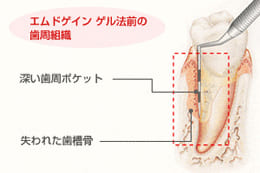

エムドゲイン法

今までの歯周病の治療は、歯石・壊死セメント質などの炎症をきたす原因物質を除去し、治癒を促すものでしたが、すでに破壊されてしまった歯周組織の再生は非常に難しいものでした。

スウェーデンで開発されたエムドゲインは、歯周外科の治療後に塗布することにより、破壊されたセメント質などの再生を図るものです。